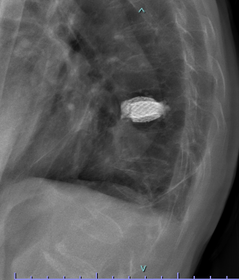

骨粗鬆性椎体骨折の癒合遷延例や偽関節例で圧潰がひどくないタイプに対しては、低侵襲なセメント治療法であるBKP(BaloonKyphoplasty:バル-ン椎体形成術)という方法で治療することが可能です。BKP治療法の適応は、原発性骨粗鬆症による脊椎椎体骨折で十分な保存的加療によっても疼痛が改善されない患者さん、および多発性骨髄腫または転移性脊椎腫瘍による有痛性脊椎椎体骨折で、既存療法に奏功しない患者さんです。

BKP治療法は脊椎椎体骨折によりつぶれた背骨に、背中側から細い針を2か所(1cm程度)差込み、骨の中で風船を膨らませて、つぶれた骨の形を元に戻した後、空いた空間に骨セメントを詰め、脊椎椎体骨折の痛みをとるという治療法です。実際には手術治療を要する多くの骨粗鬆性椎体骨折は大なり小なりの後壁損傷を認め、その場合には罹患椎体にセメント充填を行いつつ上下の椎体にスクリューを挿入してロッドで架橋することにより補強・安定化を施しています。

不安定な椎体骨折に対してはBKPに後方固定を併用して再圧潰を防ぎます。

骨折部にセメントを注入し、金属を使用して補強しています。圧潰が高度で下肢が麻痺している場合には椎体置換術を行います。

第11胸椎椎体骨折を認めます。骨折部には黒いギャップが存在し、偽関節を呈しています。軽微な後壁損傷も認めます。第1腰椎は椎体骨折後の楔状化変形を認めますが、癒合しています。

骨折部にステントの殻を挿入し、ステント内に骨セメントを充填して治療しました。背中に5mm程度の切開を2か所おいて施します。ステントにより再圧潰が防がれ、また隣接椎体に対する負担も軽減されることが報告されています。